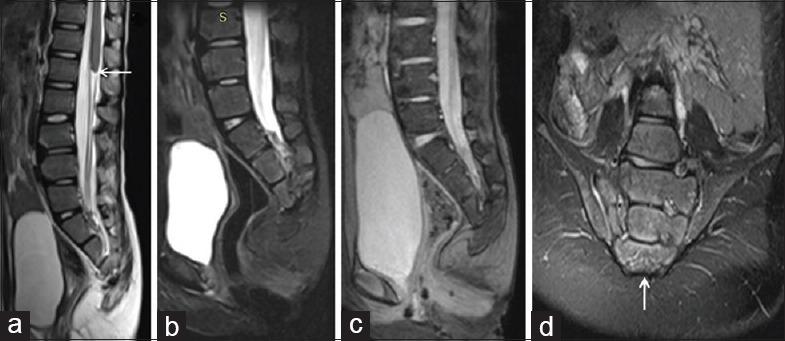

In our study, 21 pediatric patients were diagnosed with sacral agenesis/dysgenesis related to CRS. According to the Pang's classification, 2 (9.5%) patients were Type I, 5 (23.8%) patients were Type III, 7 (33.3%) patients were Type IV, and 7 (33.3%) patients were of Type V CRS. Clinically, 17 (81%) patients presented with urinary incontinence, 6 (28.6%) with fecal incontinence, 9 patients (42.9%) had poor gluteal musculatures and shallow intergluteal cleft, 7 (33.3%) patients had associated subcutaneous mass over spine, and 6 (28.6%) patients presented with distal leg muscle atrophy. MRI showed wedge-shaped conus termination in 5 (23.8%) patients and bulbous conus termination in 3 (14.3%) patients above the L1 vertebral level falling into Group 1 CRS while 7 (33.3%) patients had tethered cord and 6 (28.6%) patients had stretched conus falling into Group 2 CRS.

在我们的研究中,21例小儿患者被诊断为与CRS相关的骶骨发育不全/发育异常。根据庞氏分类,2例(9.5%)患者为I型,5例(23.8%)患者为III型,7例(33.3%)患者为IV型,7例(33.3%)患者为V型CRS。临床上,17例(81%)患者出现尿失禁,6例(28.6%)出现大便失禁,9例(42.9%)患者臀肌发育不良且臀间裂浅,7例(33.3%)患者脊柱上方有皮下肿块,6例(28.6%)患者出现小腿远端肌肉萎缩。MRI显示,5例(23.8%)患者在L1椎体水平以上出现楔形圆锥终丝,3例(14.3%)患者出现球茎状圆锥终丝,属于1组CRS;7例(33.3%)患者有脊髓栓系,6例(28.6%)患者有圆锥拉长,属于2组CRS。